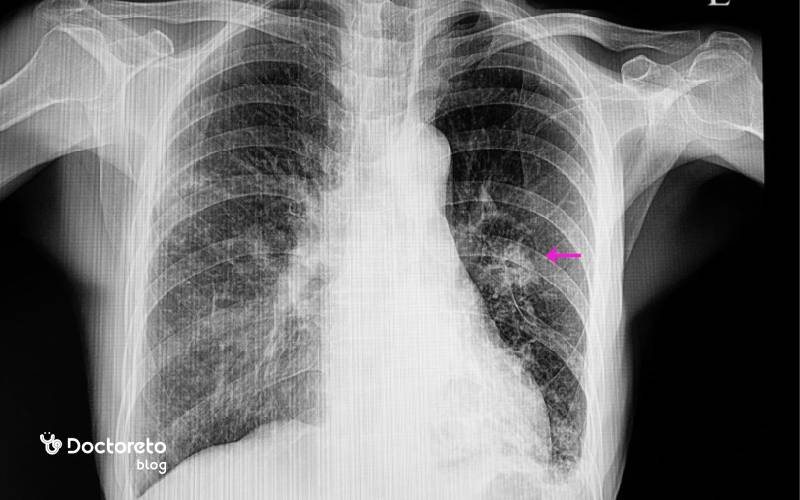

رادیولوژی عفونت ریه

رادیوگرافی قفسه سینه نخستین ابزار تصویربرداری برای ارزیابی الگوی درگیری ریه است و میتواند تراکم لوبار، ارتشاح بینابینی یا نشانههای آب آوردن ریه را نشان دهد. در موارد پیچیدهتر یا وقتی عکس ساده کافی نیست، سی تی اسکن جزئیات بیشتری از محل و وسعت التهاب و وجود آبسه یا آمپیم به دست میدهد. تفسیر دقیق تصاویر به تصمیم درباره نوع آنتی بیوتیک، نیاز به بستری یا مداخله کمک میکند. پایش تصویری در طول درمان نیز روند بهبود یا لزوم تغییر رویکرد را نشان میدهد.